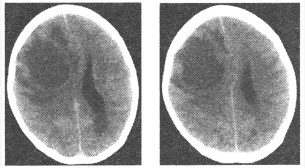

女,30岁,左侧肢体无力1周,无发热,增强CT检查如图,最可能的诊断为()

A:胶质瘤

B:脑膜瘤

C:淋巴瘤

D:转移瘤

E:脑脓肿